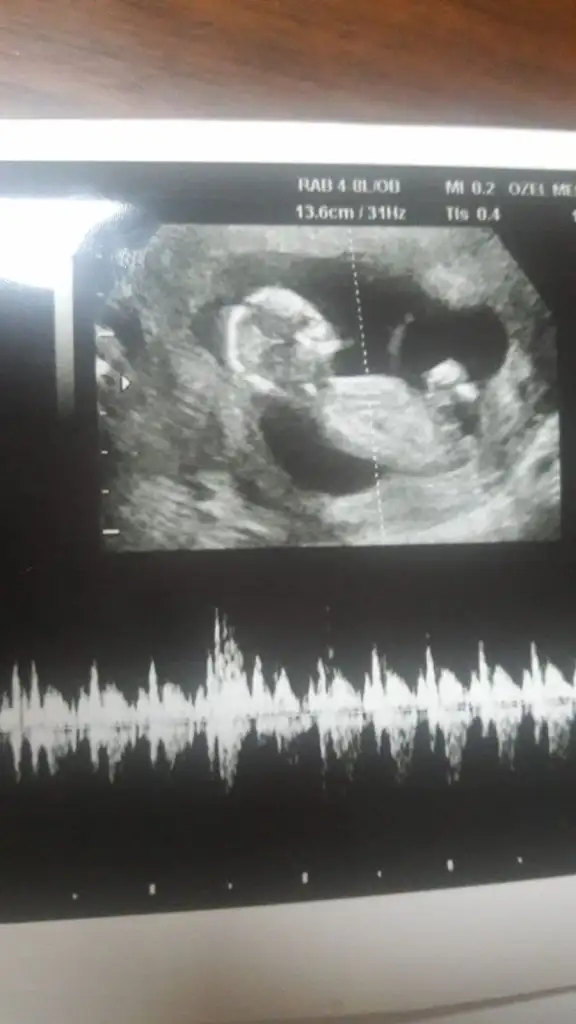

dr soylemeden siz gorun genital nub teorisi ( bebegin cinsiyeti)

Bu da venim 12 haftalık ultrasonum.Doktor bir dahaki sefere anlaşılır dedi ama tahmin edebilirseniz çok sevinirim.